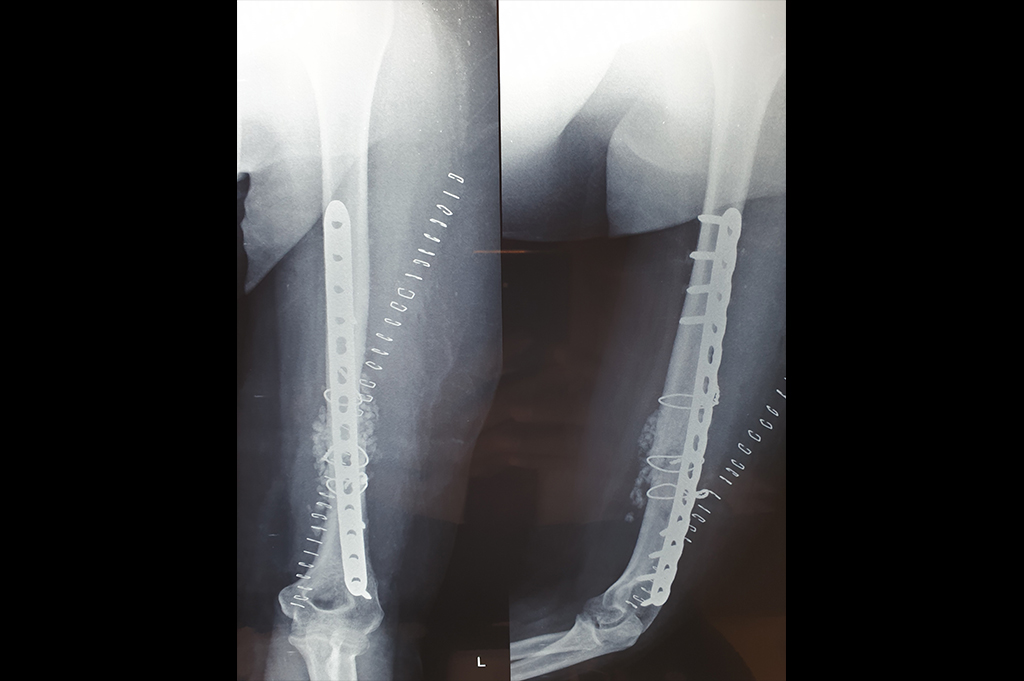

Humerus